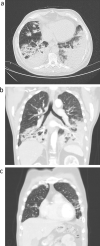

Case presentation: The case presentation describes a 58-year-old man with acute respiratory failure and bilateral lung infiltrates. Due to high inflammatory markers and a chest X-ray indicating lung infiltration, he was initially treated for pneumonia with combined antibiotics. Despite comprehensive treatment at the ICU, the patient's clinical status deteriorated rapidly, and further investigations provided a rare diagnosis of ABPC. After several days of combined corticosteroid and antifungal therapy, we observed rapid clinical improvement and subsequent resolution of the pulmonary infiltrates.

Conclusion: This case report presented a rare case of ABPC mimicking bilateral pneumonia and acute respiratory failure. Our case highlighted the importance of prompt corticosteroid and antifungal treatment initiation as it resulted in rapid clinical improvement and a near complete reversal of the bilateral lung infiltrates.